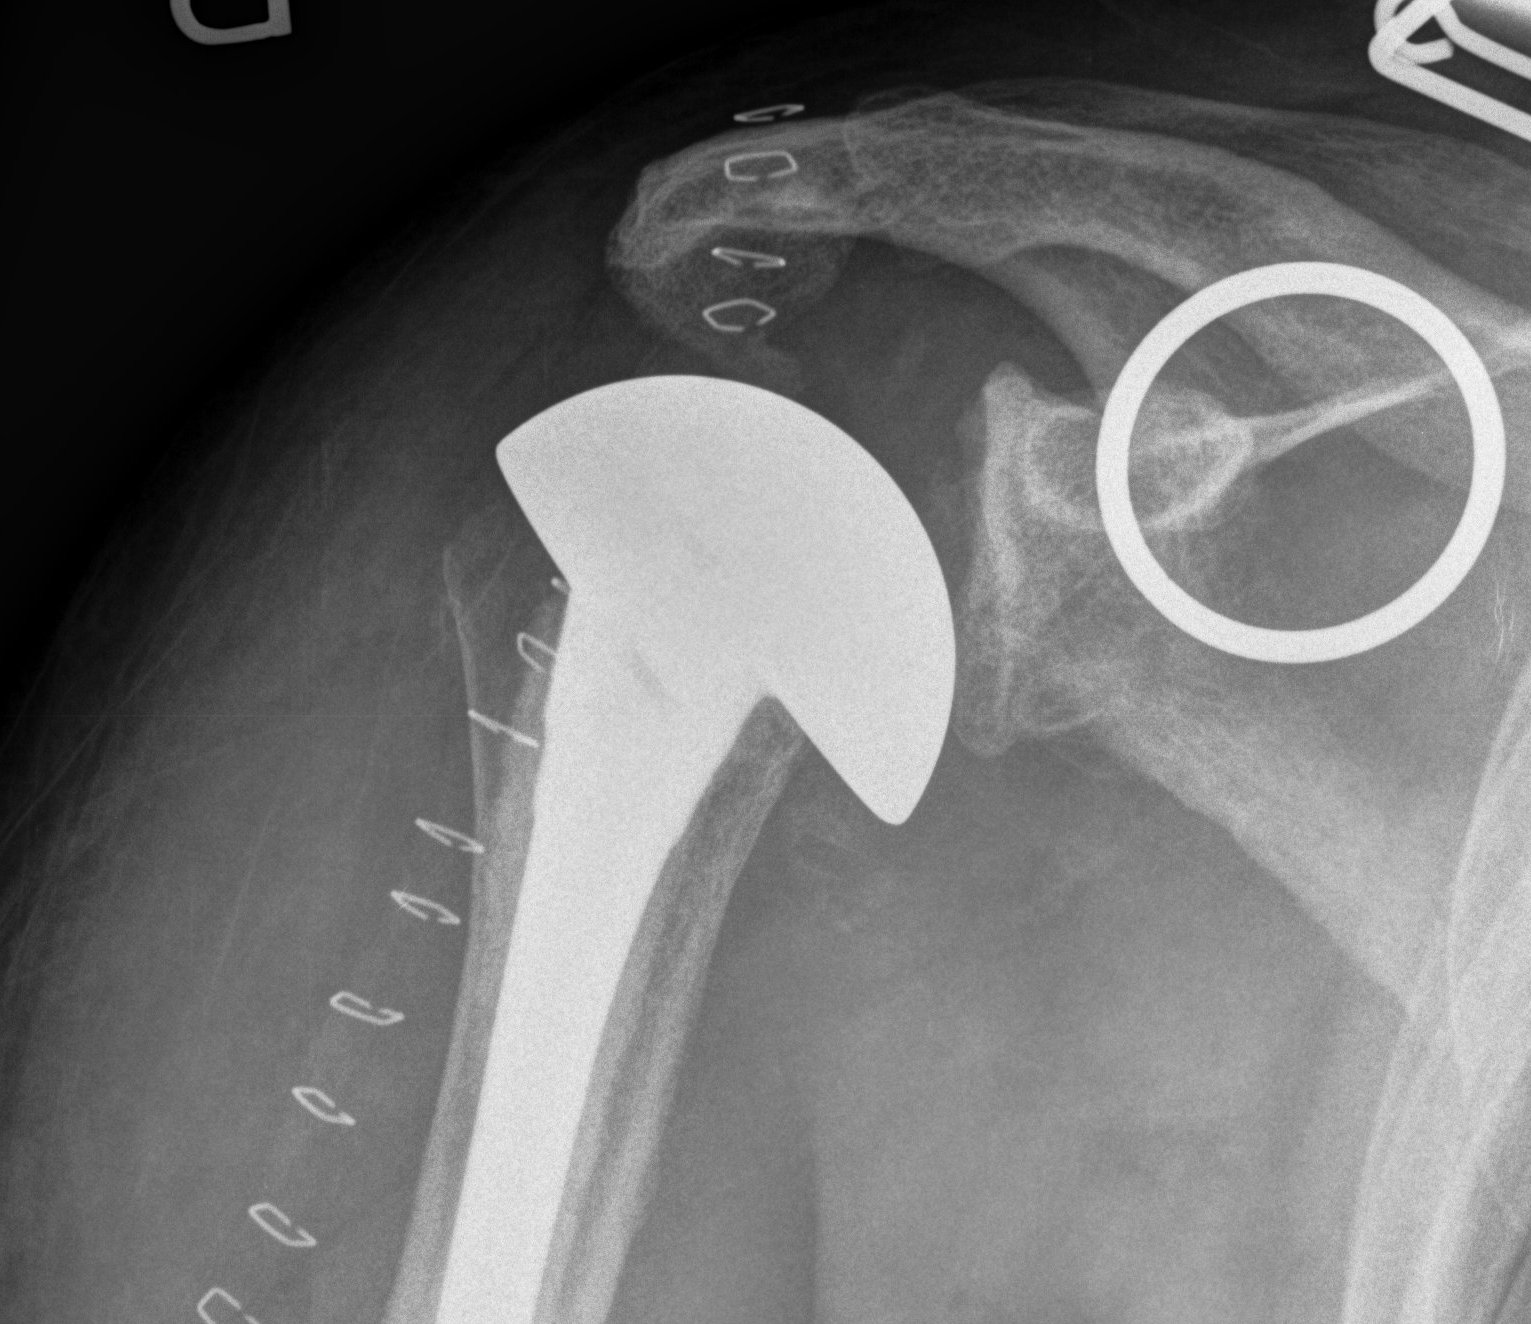

Reverse TSA

www.boneschool.com/reverse-TSA